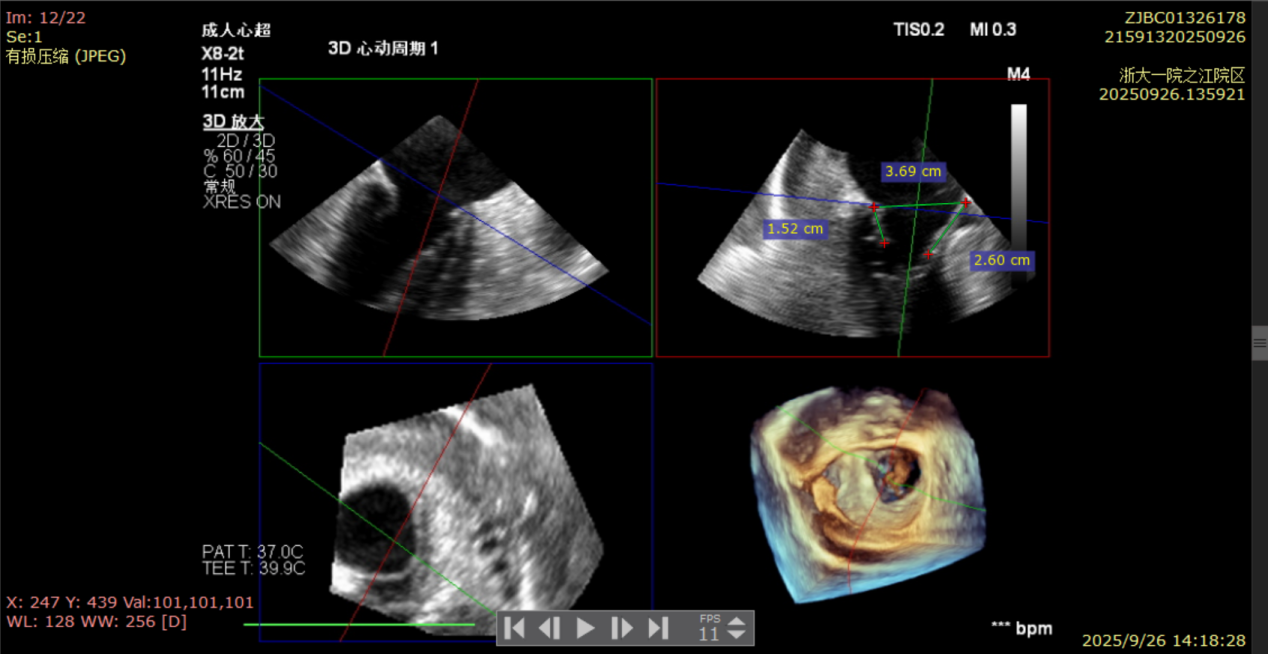

术前经食道超声显示:二尖瓣C1、P1区脱垂,重度关闭不全,彩色多普勒提示大量二尖瓣反流。术前瓣口面积MVA约5cm²,瓣环前后径AP约36.9mm,前叶A1约26mm,后叶P1约15.2mm。